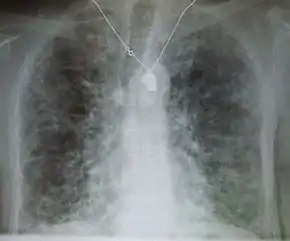

Side effects of amiodarone include various pulmonary effects.[12] The most serious reaction that is due to amiodarone is interstitial lung disease. Risk factors include high cumulative dose, more than 400 milligrams per day, duration over two months, increased age, and preexisting pulmonary disease. Some individuals were noted to develop pulmonary fibrosis after a week of treatment, while others did not develop it after years of continuous use. Common practice is to avoid the agent if possible in individuals with decreased lung function.

The most specific test of pulmonary toxicity due to amiodarone is a dramatically decreased DLCO noted on pulmonary function testing.